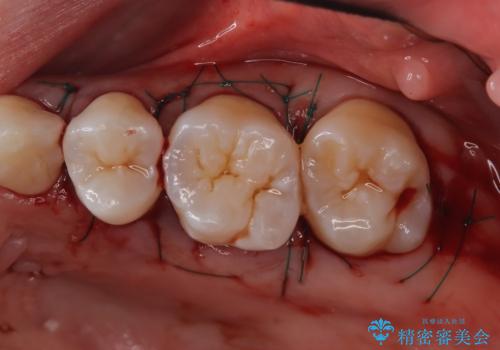

歯周ポケットがそれほど深くない患者さんでしたが、いざ歯茎を開いてみるとそこにはたくさんの歯石がありました。もし歯周ポケットが4ミリだからと言って放置していれば数年後には、沢山の骨が無くなっていたことが予期出来ます。現段階で歯茎の下にある歯石を除去することにより骨が無くなることを予防する事が出来ました。

- 外科手術のため、術後に痛みや腫れ、違和感を伴います